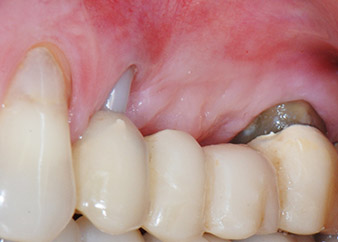

Two-months interim result

Figures 17 and 18 show the clinical result two months after the surgery. Tooth 24 exhibited reduced mobility of Miller class 1, and the soft tissues were free of inflammation. Probing was avoided at this point of time to prevent reinfection and to avoid violating the epithelial attachment. A control visit was scheduled for reentry and placement of healing abutments, six months after the insertion of the implants.